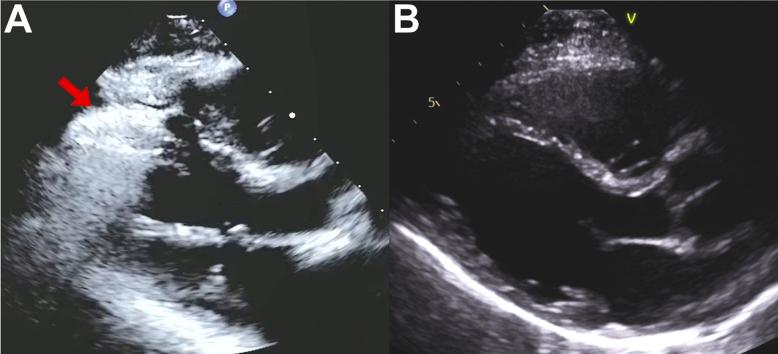

Transthoracic Echocardiography-Assisted Identification of Coronary Air Embolism During Coronary Angiography.

• CAE is a rare, high-risk morbidity and mortality event. • TTE is useful for the detection of intramyocardial air caused by CAE. • Management involves 2 core principles: increase gas diffusion and pressure.